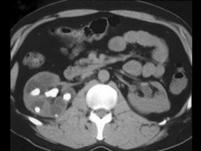

问题 女,45岁,右腰部疼痛伴血尿,请根据所示图像,选择最可能诊断 ( )

选项 A、右肾积水 B、右肾结石合并右肾盏扩张积水 C、右肾出血 D、右肾结石 E、右肾结核

答案 B